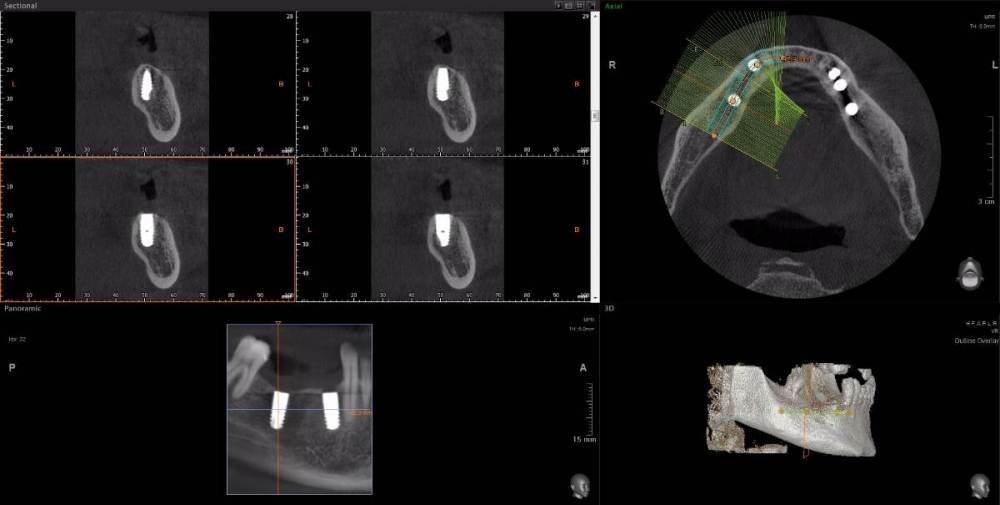

m-art-a23 Опубликовано 21 апреля, 2021 Поделиться Опубликовано 21 апреля, 2021 Здравствуйте. Два дня назад мужу установили 5 имплантов Ankylos на нижнюю челюсть (2+3). Спустя 30-40 мин после операции появилась сильная острая боль, которая не уменьшается по настоящее время. Боль похожа по ощущениям на пульпитную, не снимается никакими НПВС, кроме кеторолака. А/б, А/гистаминные, холод местно, хлоргексидин - все рекомендации выполнялись. На осмотре врачом не обнаружено следов воспаления, КТ сделал - без особенностей. Что может служить причиной такой боли, сколько она может длиться и что делать в данной ситуации? Врач-имплантолог ничего внятного не предложил. Ссылка на КТhttps://cloud.mail.ru/public/EvKn/ULqxLy6BD Ссылка на комментарий

wladdX Опубликовано 21 апреля, 2021 Поделиться Опубликовано 21 апреля, 2021 (изменено) Вы не указали локализацию болей, слева или справа? Левая сторона Справа Изменено 21 апреля, 2021 пользователем wladdX 1 Ссылка на комментарий

red_butler Опубликовано 22 апреля, 2021 Поделиться Опубликовано 22 апреля, 2021 7 минут назад, m-art-a23 сказал: Нет, не один. Но он лучший. Скажите пожалуйста, что служит причиной боли, по-Вашему? Неужели все импланты нужно убирать только по Кт трудно судить, но есть вопросы по позиционированию имплантов... боль может быть вызвана перегревом кости во время формирования ложа импланта, но в этом случае она появляется примерно с третьего дня. Так же боль может вызывать гиперкомпрессия импланта, и может болеть кость если ее придавили формирователем десны. Я бы обсудил с хирургом удаление среднего импланта слева 1 Ссылка на комментарий

Irouil Опубликовано 22 апреля, 2021 Поделиться Опубликовано 22 апреля, 2021 Я бы рекомендовал удаление среднего импланта слева, независимо от наличия/отсутствия болевых ощущений боль может быть признаком каких-то описанных моим коллегой процессов, а может ничего кроме самой боли не означать (менее вероятно, но и такое бывает). Если удаление упомянутого импланта поможет против болевого синдрома - это win-win если хирург не видит необходимости удаления импланта, я бы рекомендовал сходить на осмотр к ортопеду, который будет в будущем эти импланты протезировать. Возможно у него найдутся весомые аргументы для коллеги 3 Ссылка на комментарий

Irouil Опубликовано 22 апреля, 2021 Поделиться Опубликовано 22 апреля, 2021 (изменено) 1 час назад, m-art-a23 сказал: Благогдарю за совет. Если Вам не трудно, объясните пожалуйста, что не так со средним имплантом. Описанные процессы, если таковые имеют место быть, должны постепенно прийти в норму? Другими словами, сколько еще нужно времени, чтобы окончательно принять решение об удалении импланта (имплантов)? Сегодня третьи сутки после установки. Боль сохраняется. Средний имплант расположен чрезвычайно близко к соседнему, расположенному кпереди от него. С очень большой долей вероятности это может привести к значительной резорбции (убыли) костной ткани между ними, что для любых имплантов очень вредно, а для конкретно Анкилосов - губительно из-за особенностей их протезирования. Если неблаготворные процессы (компрессионный или термический некроз) присутствуют, то импланты просто не интегрируются (не приживутся) - те, что зашиты не выдержат нагрузки при раскрытии, а тот, на котором стоит ФДМ - расшатается через 2-3 недели. Это не призыв проверять его стабильность языком, сейчас его лишний раз лучше не трогать. В норме после имплантации боли держатся 1-2 дня, если все не очень хорошо - держатся 2-3 недели, но даже в таком случае имплант может интегрироваться, поэтому решение об его удалении в таком случае должно, по моему убеждению, быть совместным между врачом и пациентом, и приниматься в индивидуальном порядке Изменено 22 апреля, 2021 пользователем Irouil Ссылка на комментарий